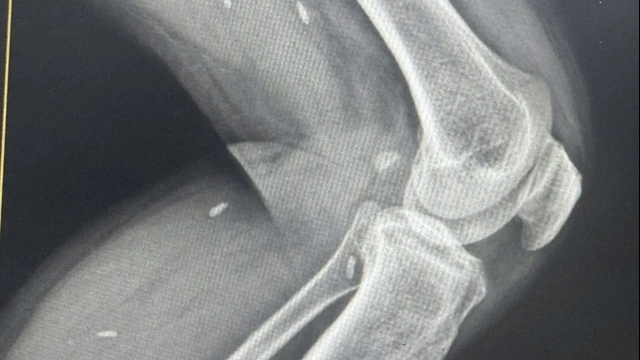

Cánh tay phải của bệnh nhân cũng có vết thương sâu dài 10cm, máu phun thành tia, nghi ngờ đứt toàn bộ động mạch và thần kinh cánh tay. Bên cạnh đó, bệnh nhân còn có vết thương tại vùng đùi phải dài khoảng 10cm nghi ngờ tổn thương nhánh tĩnh mạch đùi phải, vết thương phần mềm đùi trái và vết thương bàn tay trái.

Theo BSCKII Lê Thanh Hoài – Phó trưởng khoa Ngoại tổng hợp 1 chia sẻ: "bệnh nhân có nhiều vết thương mạch máu, đặc biệt vết thương rách tĩnh mạch chủ dưới, đứt động mạch cánh tay nghiêm trọng dẫn đến mất máu rất nhiều. Do đó, chúng tôi dồn toàn lực hồi sức tích cực toàn diện, bao gồm hỗ trợ thở máy, điều chỉnh toan máu, kiểm soát thân nhiệt và rối loạn đông máu, điều chỉnh thuốc vận mạch để kiểm soát huyết áp và đảm bảo tưới máu cho các cơ quan quan trọng.

Trước, trong và sau phẫu thuật bệnh nhân được truyền tổng cộng 65 đơn vị máu và chế phẩm máu (tương đương khoảng 11 lít máu) để bù đắp lượng máu mất và duy trì tuần hoàn. Đây là trường hợp có chấn thương nghiêm trọng, mất máu nhiều, nguy cơ tử vong cao, tính mạng người bệnh tính bằng phút, nên bắt buộc phải thực hiện phẫu thuật cùng lúc để rút ngắn thời gian phẫu thuật, kiểm soát cầm máu tốt hơn, tăng tỷ lệ cứu sống bệnh nhân."